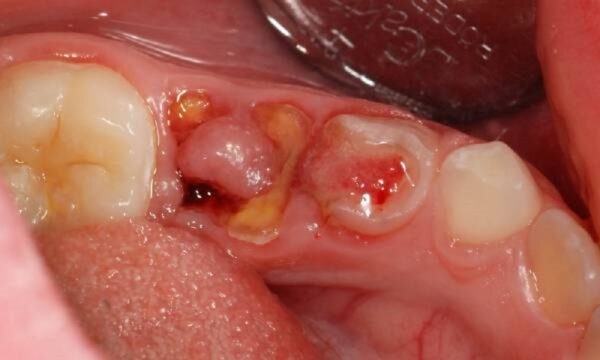

Vết áp xe trên răng gọi là răng sâu lồi thịt. Đây là tình trạng viêm nhiễm cấp tính với mức độ nặng. Dấu hiệu của bệnh là sự bùng phát niêm mạc dưới nướu, tạo thành một cục mô mềm đẩy lên. Từ đó, gây ra một cảm giác đau không thể ăn và ngủ được. Không chỉ dừng lại ở đó, cục mô này còn có khả năng tạo mủ và gây nhiễm trùng, kèm theo biểu hiện sốt.

Sâu răng lồi thịt là tình trạng gì? (minh họa)